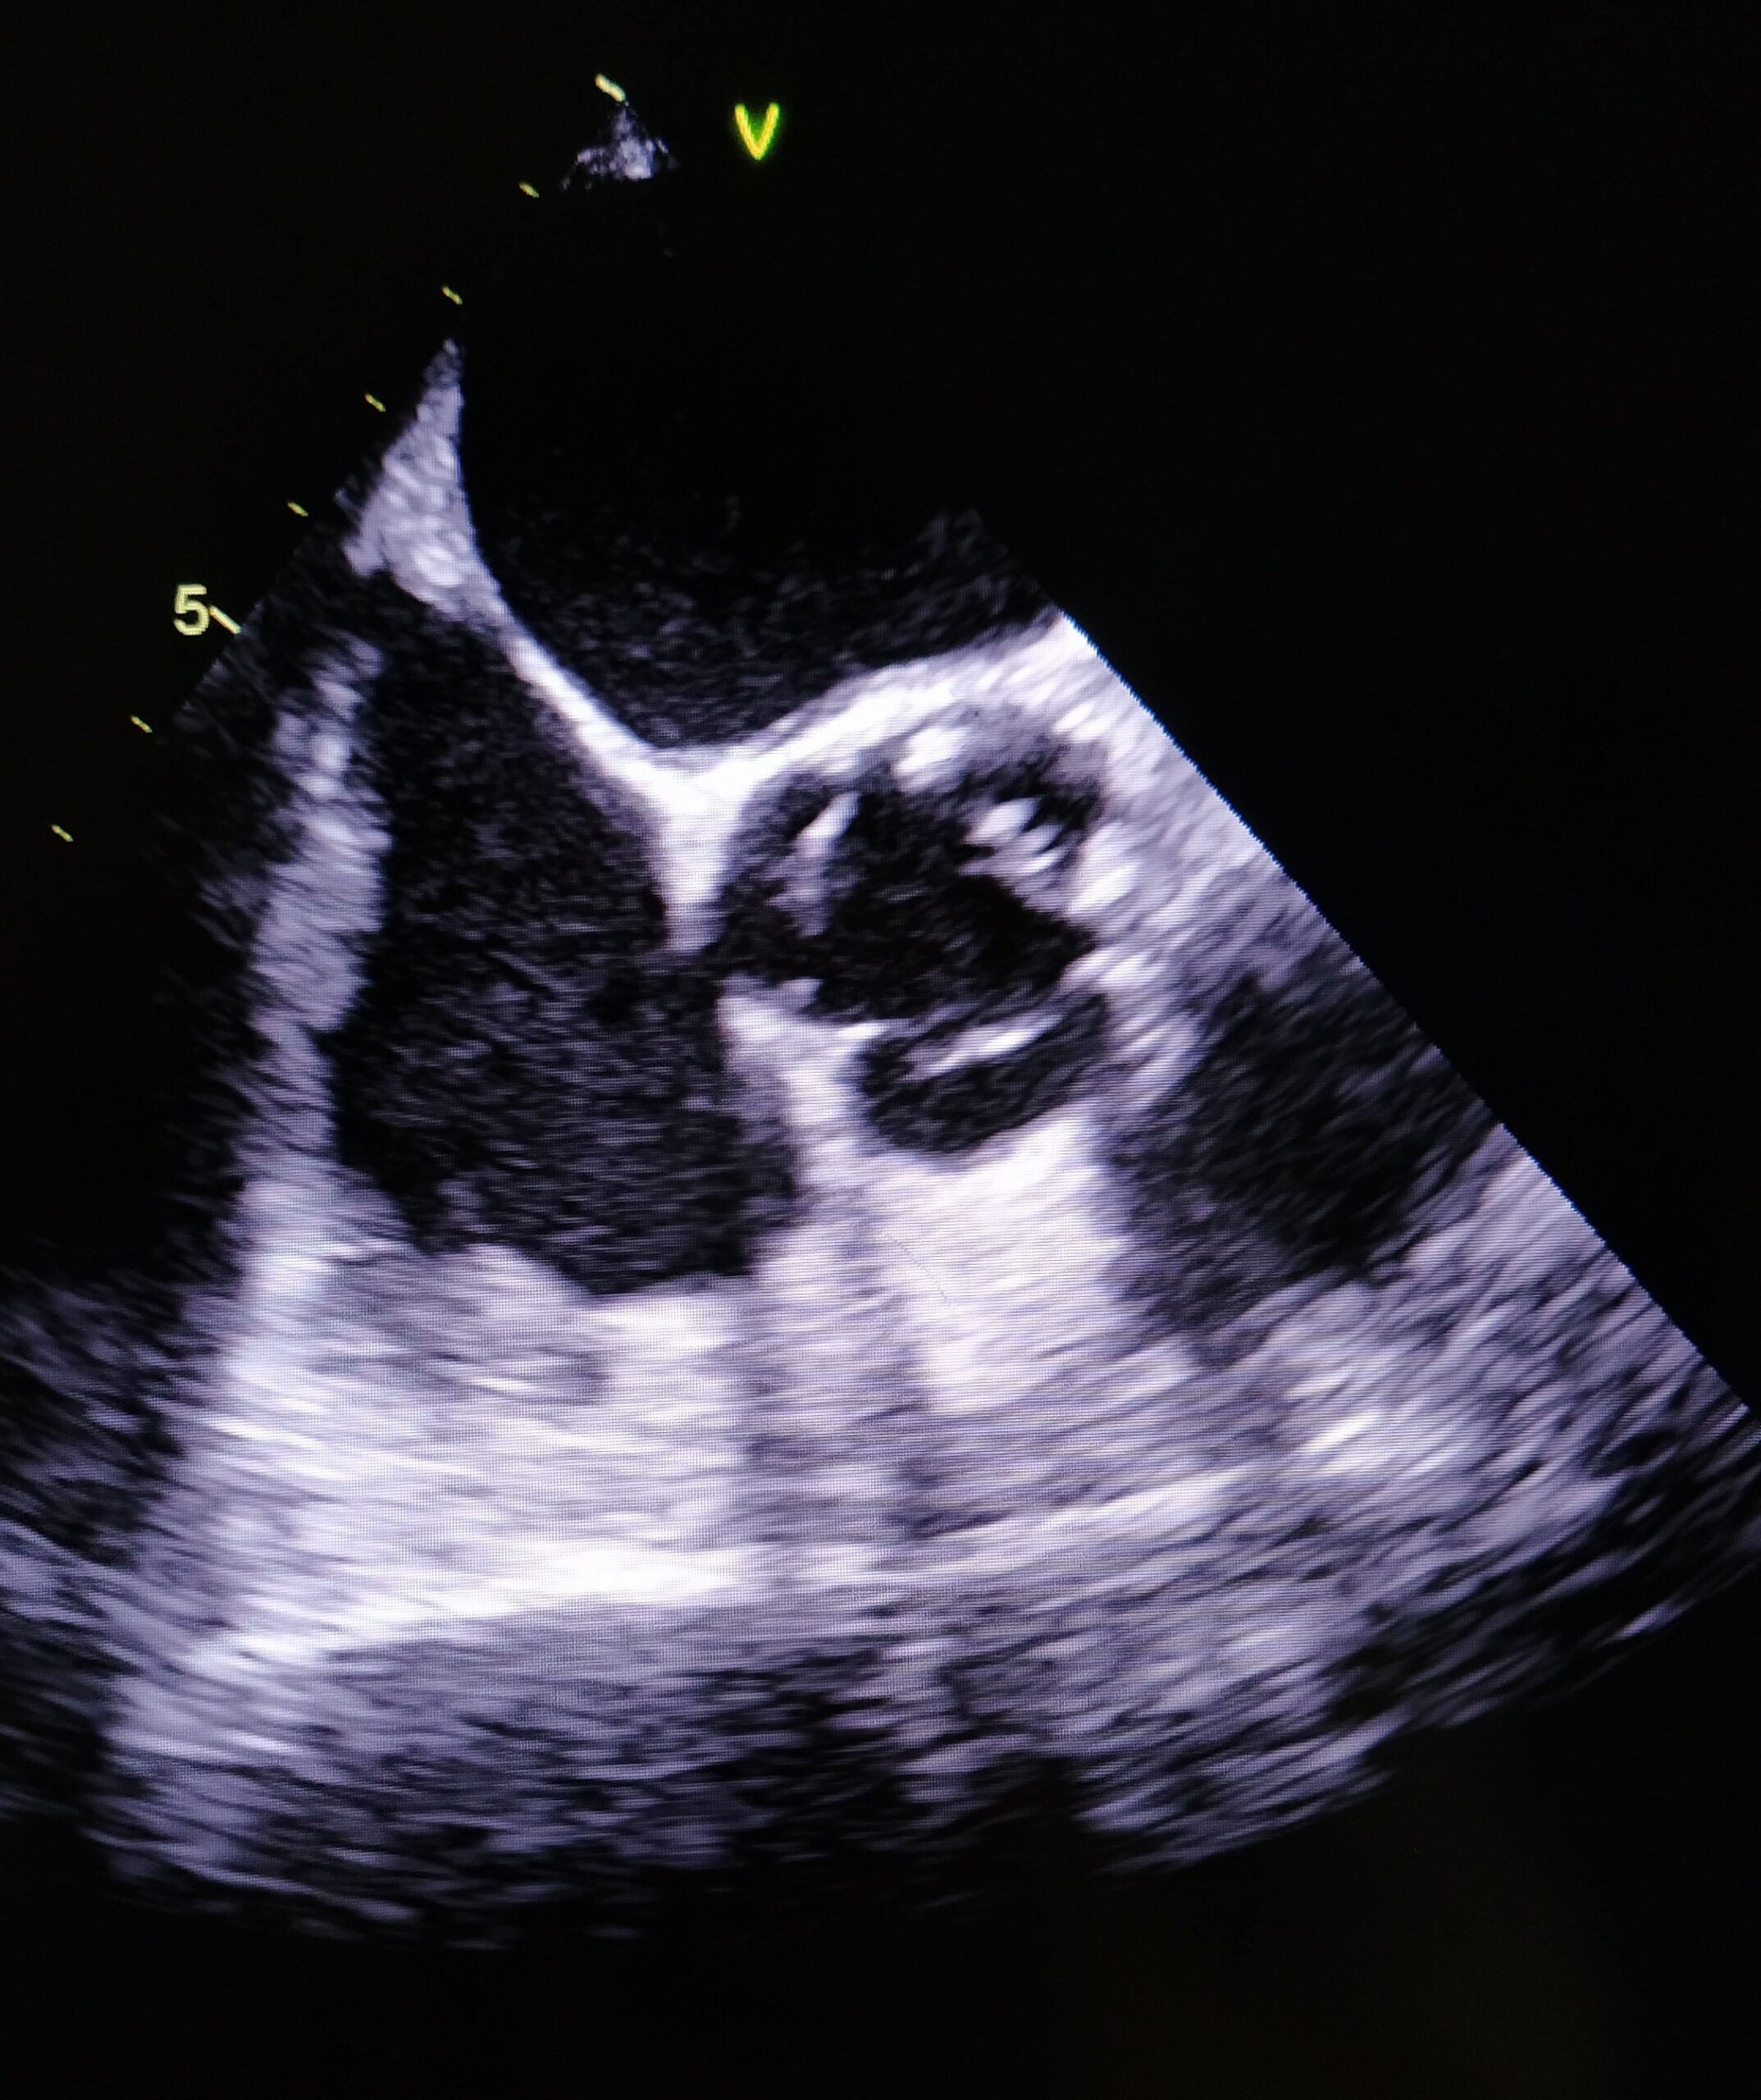

Resim 1a. Aort Kapağı Üzerinde Oklarla Gösterilen Vejetasyonun Transtorasik Ekokardiyografi (TTE) Görüntüsü

Üç farklı zamanda alınan üç set kan kültüründe aynı etkenin üremesi, kalıcı kateterin geç çekilebilmesi ve aort odağında yeni gelişen bir üfürüm duyulması nedeniyle bakteriyeminin 11. gününde yapılan transtorasik ekokardiyografi (TTE)’de aort kapakta ventrikül tarafında 0.9 × 0.6 cm boyutlarında vejetasyon saptandı (Tablo 1, Resim 1a-1b). Kültür ve TTE sonuçlarıyla iki majör kriteri sağlayan hastaya S. maltophilia endokarditi tanısı kondu.